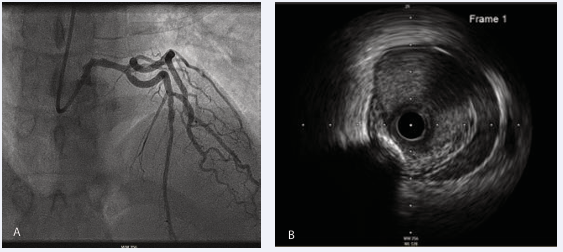

In November 2024, she returned with chest pain, anterior ST elevation on ECG. She was taken directly to the cardiac catheterization lab where angiography showed TIMI 3 flow in the left main stem (LMS) and LAD but an appearance in keeping with haematoma formation in the LAD. Intravascular ultrasound (IVUS) showed haematoma in the proximal LAD extending to the LMS (Figure 2).

Figure 2: Following presentation in 2024. (A) Anterio posterior cranial imaging during coronary angiography demonstrated features in keeping with in-stent restenosis. (B) Intravascular Ultrasound (IVUS) confirmed haematoma in the proximal LAD.